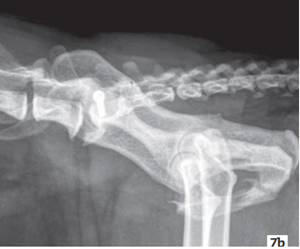

Des radiographies du bassin (face et profil) sont réalisées en phase postopératoire (Photos 7a et 7b). La réduction de la DSI est satisfaisante et restaure la symétrie du cadre du bassin.

photo 7a photo 7b

Photo 7a - Incidence de face (ventro-dorsale)

Photo 7b - Incidence de profil

Photos 7a et 7b - Images radiographiques postopératoires.

La symétrie du cadre du bassin est restaurée.